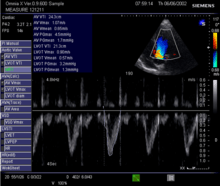

Echocardiography

Echocardiography is a non-invasive method of quantifying cardiac output using ultrasound. Two-dimensional (2D) ultrasound and Doppler measurements are used together to calculate cardiac output. 2D measurement of the diameter (d) of the aortic annulus allows calculation of the flow cross-sectional area (CSA), which is then multiplied by the VTI of the Doppler flow profile across the aortic valve to determine the flow volume per beat (stroke volume, SV). The result is then multiplied by the heart rate (HR) to obtain cardiac output. Although used in clinical medicine, it has a wide test-retest variability.[5] It is said to require extensive training and skill, but the exact steps needed to achieve clinically adequate precision have never been disclosed. 2D measurement of the aortic valve diameter is one source of noise; others are beat-to-beat variation in stroke volume and subtle differences in probe position. An alternative that is not necessarily more reproducible is the measurement of the pulmonary valve to calculate right-sided CO. Although it is in wide general use, the technique is time consuming and is limited by the reproducibility of its component elements. In the manner used in clinical practice, precision of SV and CO is of the order of ±20%.